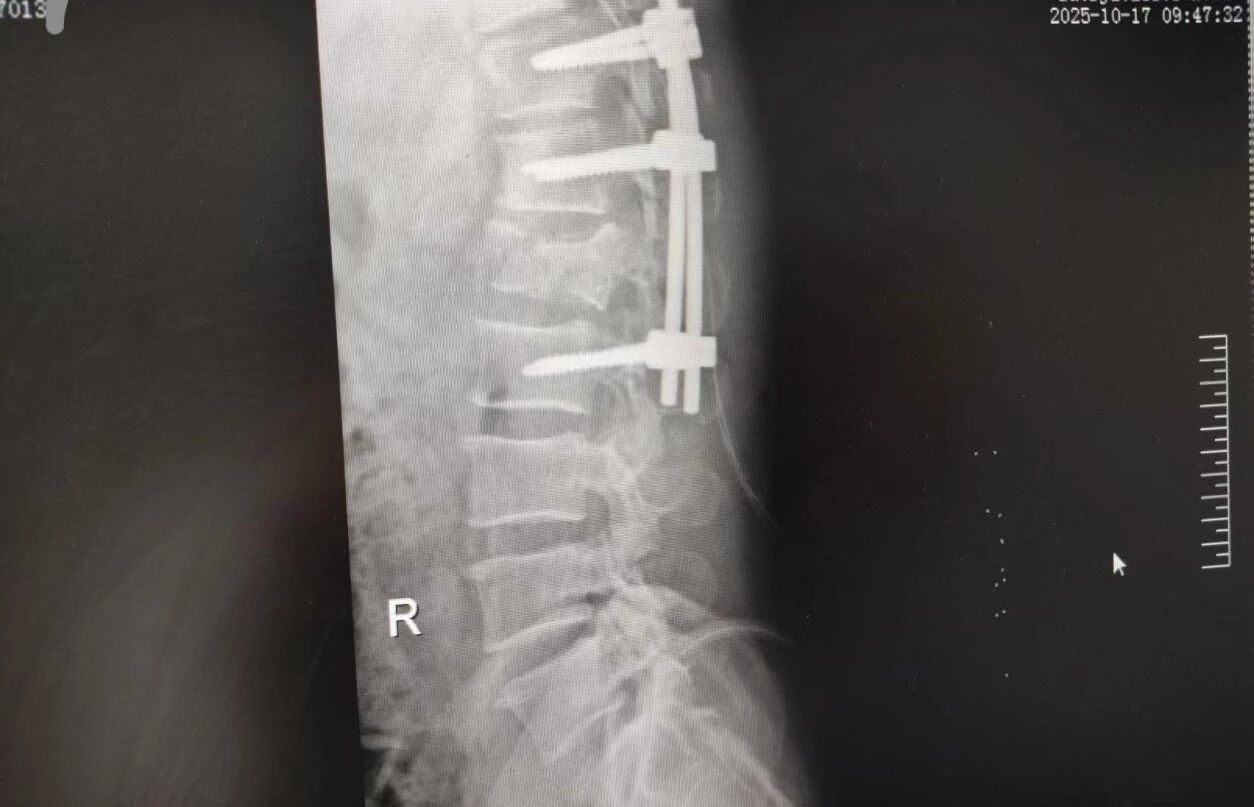

針對腰椎傷情,骨科竇志剛醫生團隊緊急開展腰 1 椎體爆裂性骨折切開復位內固定術 + 椎板切除減壓術。手術室、麻醉科無縫銜接開通綠色通道,手術團隊快速就位,術后患者下肢活動恢復自如。